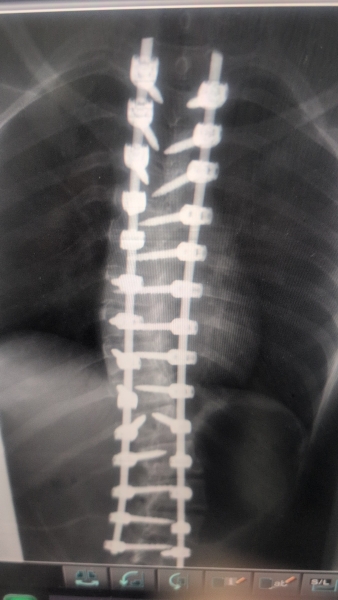

بتوجيهات معالي وزير الصحة إبراهيم البدور، ومتابعة مدير مستشفيات البشير الدكتور الإنسان علي العبدالات، نجح النِّطاسي المبدع الدكتور جاسر الزبيدي في تنفيذ عملية جراحية دقيقة ومعقّدة لإصلاح تشوّه في العمود الفقري لطفلة كانت تعاني من حالة صحية معقّدة.

وجاءت العملية الجراحية بعد تقييم طبي شامل ودقيق للحالة، حيث استخدم الفريق الجراحي أحدث التقنيات المتخصصة في جراحات العمود الفقري، ما أسهم في تصحيح التشوّه وتحسين الاستقرار الوظيفي، وسط متابعة حثيثة لمراحل ما قبل وما بعد الجراحة.

وأكدت إدارة المستشفى أن العملية تكللت بالنجاح، وأن حالة المريضة مستقرة وتخضع حاليًا لبرنامج تأهيلي متكامل، مشيدةً بالكفاءة العالية للفريق الطبي والتمريضي، وبالدعم المتواصل الذي توليه وزارة الصحة للارتقاء بالخدمات الصحية التخصصية.

حيث كانت الطفلة تعاني منذ سنوات من تشوّه خلقي في العمود الفقري، الأمر الذي انعكس سلبًا على قدرتها على ممارسة حياتها اليومية بشكل طبيعي، وتسبب لها بآلام وتحديات صحية مستمرة، إلى أن تكللت الجهود الطبية بإجراء هذه العملية الجراحية الدقيقة التي أعادت لها الأمل بتحسّن نوعية حياتها.